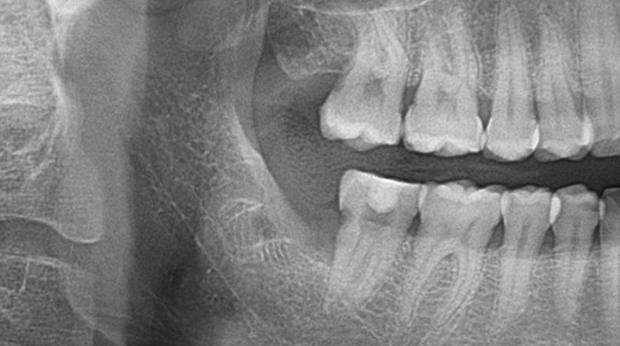

매복 사랑니 발치

임플란트와 사랑니 발치는 외과적 시술로 잇몸을 절개하는 외과적 시술은

짧으면 짧을 수록 시술 후 붓기와 통증이 최소화됩니다.

치과의사 경력 14년차 구강외과 전문의가 빠르고 안전하게, 아프지 않게 수술해 드립니다.

치과경력 14년차 구강외과 전문의

연세대학교 치과대학 구강외과 임상 조교수